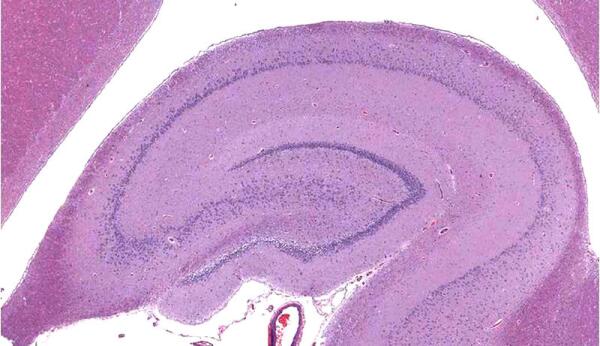

Потеря памяти, способности концентрации внимания, ориентации на местности и в виртуальной реальности, депрессия, слабоумие, некоторые формы эпилепсии, старческого маразма, идиотии — это все он в ретрограде. Когда он ссыхается, уменьшается в размере, тогда мы, как в старом анекдоте, забываем, что у нас эклер потому что у нас таки склероз. Объем гиппокампа естественным путем уменьшается с возрастом. Отсюда и «моменты возраста».

И вот он, третий аргумент. Из Северной Каролины. Вот что установили ученые: чем выше степень религиозности людей, тем меньше у них объем гиппокампа. И, следовательно, тем больше проявлений, связанных с усыханием этого участка проблем: сильнее деменция, депрессия, стресс, поражение абстрактного мышления, навигации и прочих радостей жизни.